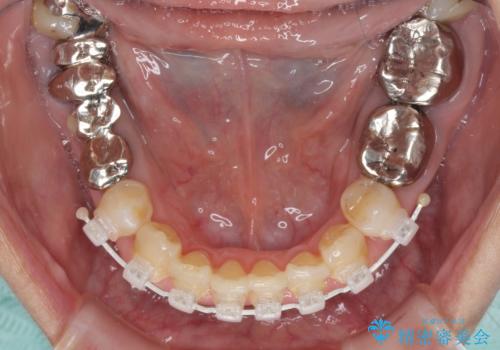

- 矯正装置

- 審美装置

補綴治療に先立ち、下顎前歯の部分矯正を行い、前歯の咬み合わせの安定性向上を図りました。

相談の上、最も気になっている前歯の部分矯正と補綴治療により口元の改善を図ることとしました。

審美面と合わせて清掃性も改善され、患者様には大変満足していただきました。